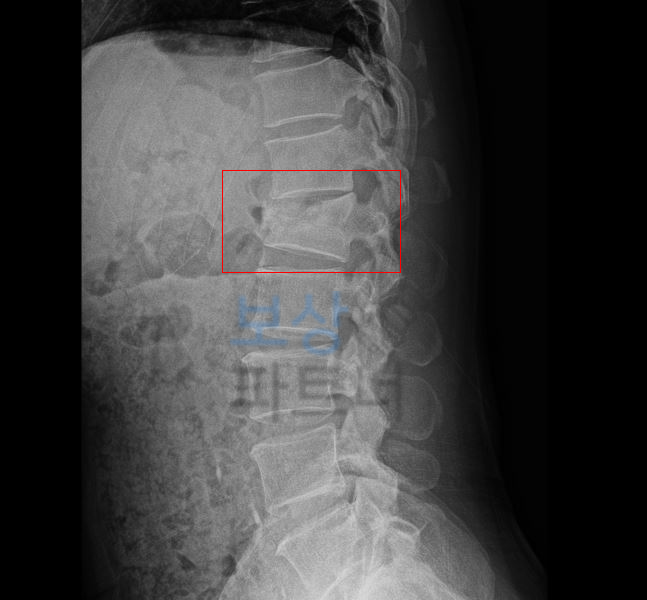

이 사고로 이@@님은 **L1 부위의 골절 S3202 **진단을 받아 최소 12주간의 침상안정이 필요했는데요 L1 부의의 골절은 lumbar 의 약어로 요추 1번 부위의 골절을 의미합니다.

부산 손해사정사 lumbar 즉 L1 부위의 골절 보험 처리